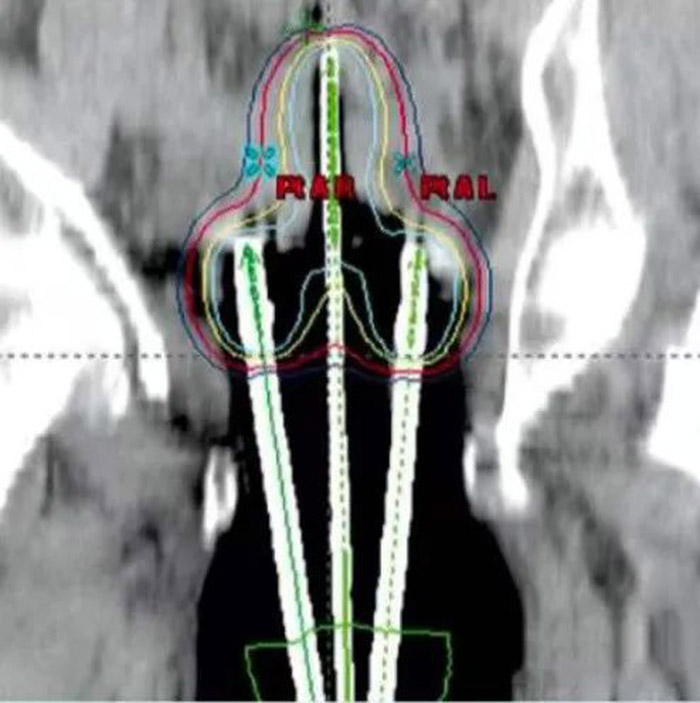

CT定位图像:人体中的施源器

相较于高能量X射线从体外照射肿瘤的“外照射放疗”,“内照射放疗”是将放射源准确地放置于癌变肿瘤的区域,定位精准、照射科学,影响范围只局限于放射源周围的有限区域,有效减少正常组织受到的照射量。同其他放射治疗技术相比,“内照射放疗”的疗程更短,有助于降低癌细胞在每次治疗间隙中分裂与生长的概率。